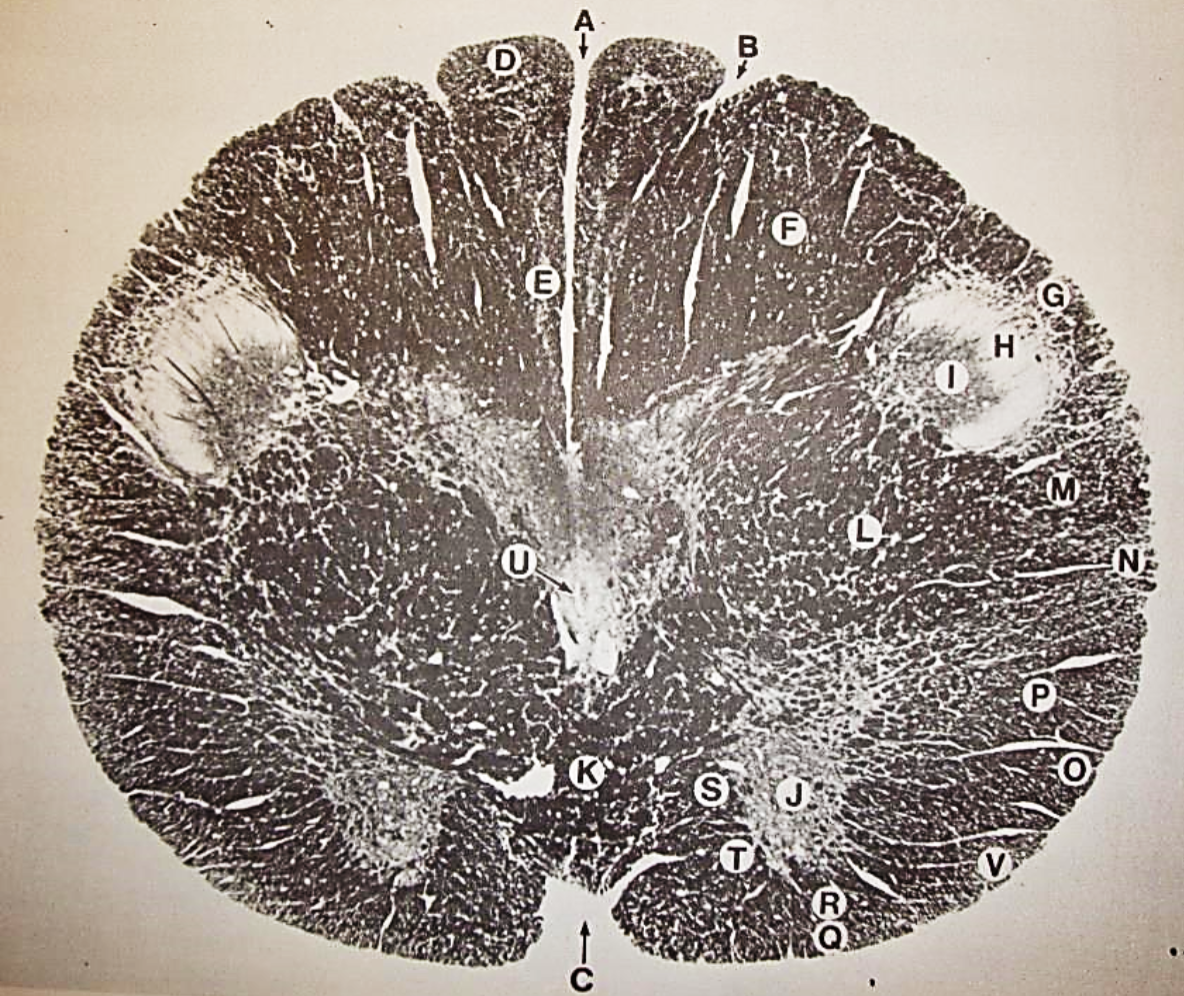

A

Fasciculus gracilis

B

gracile nucleus

C

fasciculus cuneatus

D

cuneate nucleus

E

spinal trigeminal tract

F+G collectively

spinal trigeminal nucleus

H

accessory nucleus

I

pyramidal decussation

J

rubrospinal tract

K

posterior spinocerebellar tract

L

anterior spinocerebellar tract

M

lateral spinothalamic tract

N

anterior spinothalamic tract

O

lateral vestibulospinal tract

P

medial longitudinal fasciculus

Q

tectospinal tract